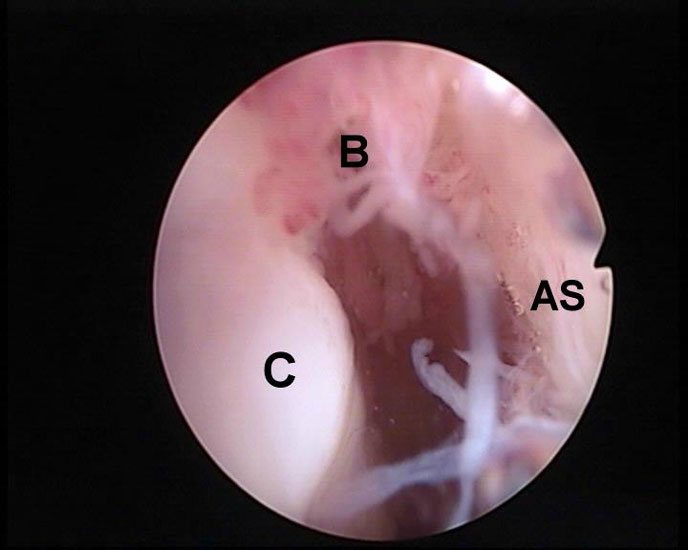

Abbildung 5-7, Video 2

Zunächst wird die Bursektomie (Abb. 5: gerötete Bursa subachillea; C=Calcaneus, B=Bursa, AS=Achillessehne) mit der Radiofrequenzsonde durchgeführt und die Haglundexostose dargestellt. Alternativ kann die Bursektomie mit einem Shaver durchgeführt werden. Hierbei sollte der Ansatz der Achillessehne kaudal einsehbar sein (Abb. 6: C=Calcaneus, AS=Achillessehne) und unbedingt die gesamte mediolaterale Ausdehnung der posterioren Calcaneusfläche erfasst werden (Abb. 7). Häufig liegen Anteile der Exostose weit medial und/oder lateral und werden übersehen.